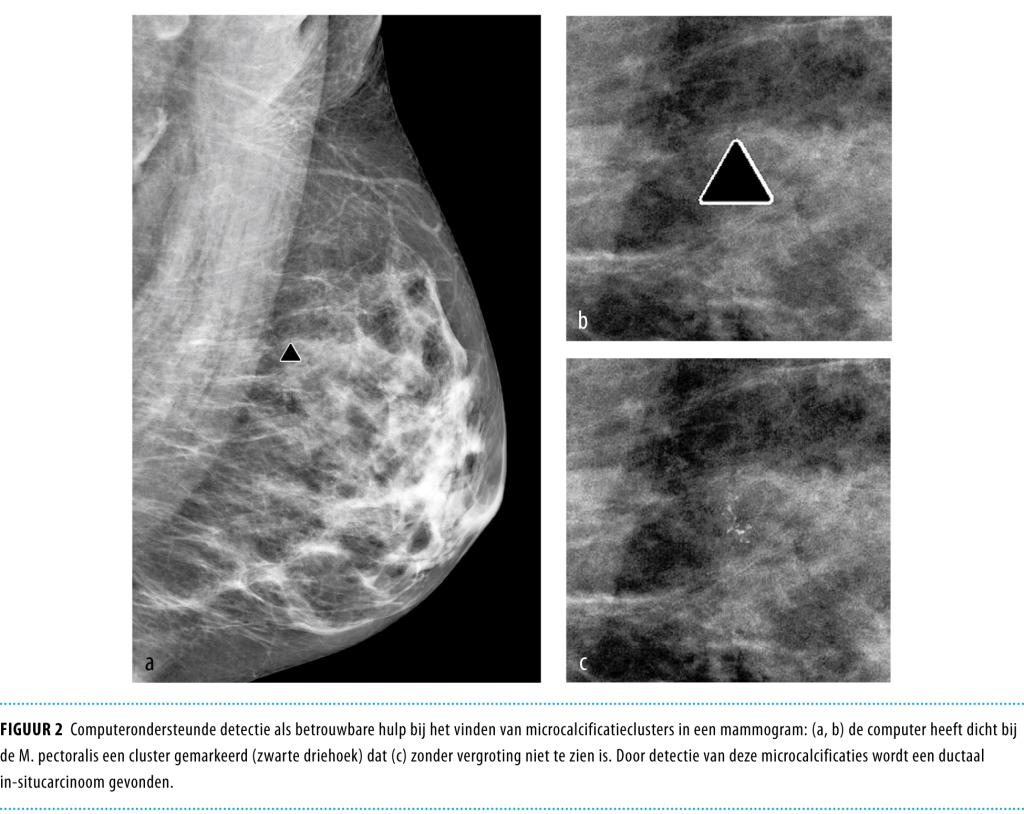

• Als alternatief kan de computer worden ingezet om afwijkingen op te sporen. Computerondersteunde detectie (CAD) wordt in sommige landen al op grote schaal toegepast. Het ligt in de rede om CAD naast de huidige dubbele beoordeling in te zetten.